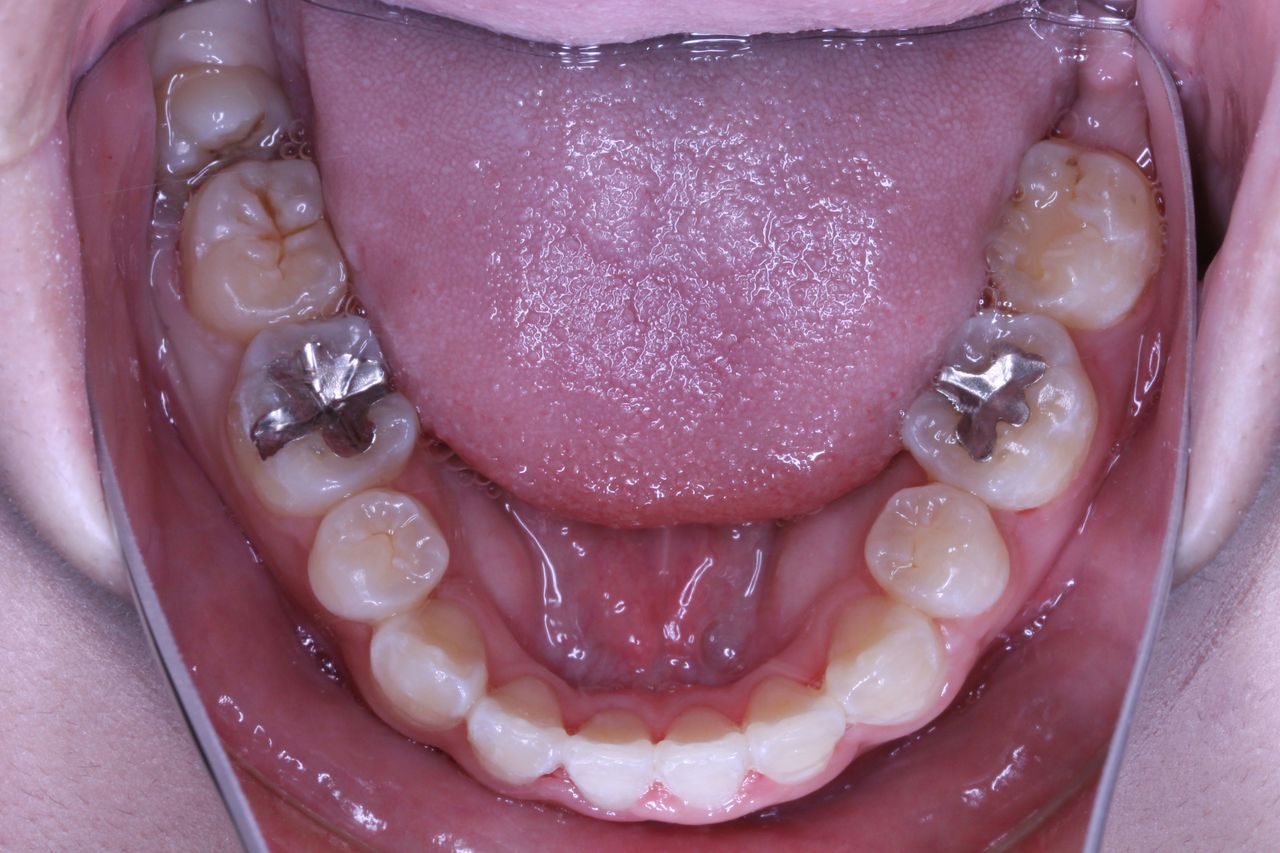

5:銀歯など多数生えていてそちらを抜歯したほうが自分の白い歯を多数のこせる場合

上の奥歯の部分を注目してください。親知らずの前の歯が2本抜歯してるのがわかると思います。

つまり、この時点で上顎だけで3本も抜歯してます。そういう意味では患者さんは不安になりますかね(笑)